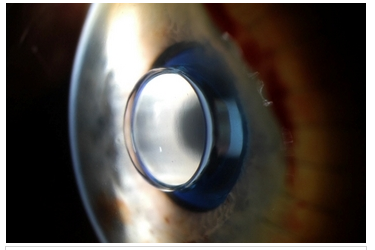

Но совсем недавно я узнал, что существует еще один метод, принципиально отличающийся от всего этого, но в тоже время чрезвычайно логичный и на удивление рабочий. Фантастический для меня по своему принципу работы, но имеющий свои минусы. Возможно для вас это не новость, но если я вас заинтриговал, то добро пожаловать под кат.

Главный невероятный плюс — у вас будет зрение единица без операции, и без каких-либо дополнительных приспособлений.